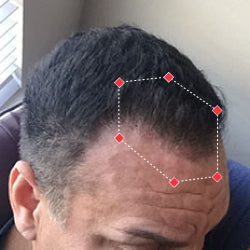

Indications for Use

The iRESTORE Hair Growth System Elite is indicated to promote hair growth in males who have Norwood-Hamilton Classifications of IIa to V and in females who have Ludwig-Savin Classifications I to II, and in both with Fitzpatrick Skin Phototypes I to IV. In other words, iRESTORE is not intended for people who are bald or have advanced hair loss.

Laser therapy works to reactivate thinning and dormant hairs. For completely bald areas of the scalp, there may be no way to promote hair regrowth. If you still have hair follicles, laser therapy may be beneficial to you.

Not sure? Email us to have our specialists evaluate your scalp conditions to see if iRESTORE is suitable for you.